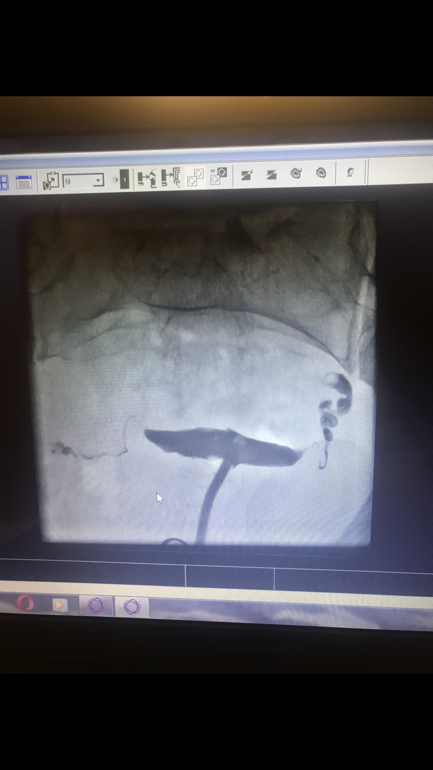

Анализы и процедуры. Помощь в расшифровке результатовВсем доброго вечера. Такой вопрос, год назад гсг, лечение антибиотиками, после неё два пролетных эко. В заключении ничего внятного кроме непроходимости и воспаления не написали. Эти мысли не дают покоя. На диагност лапару хотела идти, но уже 4 наркоза за пол года. Все врачи отговаривают.

ОТЧЁТ : ну что ж, сделала я операцию, только не лапару а обычную( хирург так посчитала нужным) . До операции прошли стимуляцию и в крио ушли 6 отличников))). Ну и вот лежу в больнице и вспомнила свой пост и как сама искала ответы. На узи труб видно не было, и смотрели хорошие специалисты. Но хирург на ощуп сказала и по этому фото что я оставила после гсг что будем оперировать. Мы договорились, если можно оставить, то оставлят. Итог : трубы все в спайках, в обоих трубах жидкость - гидрос, расширенные всего до 1 см и выглядели как сосиски. Удалили без раздумий. Это была причина моей ЗБ !!!